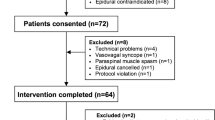

The study was conducted from July 2013 to December 2014 at our tertiary care hospital. After institutional ethics committee approval (November 2013) and written informed consent, 26 adult (> 18 yr) patients with American Society of Anesthesiologists physical status I and II who were scheduled to undergo thoracic surgery requiring thoracotomy for pneumenectomy, lobectomy, and/or decortication were enrolled in this prospective observational study. Exclusion criteria included patient refusal, contraindications to epidural blockade (i.e., bleeding diathesis, neurological or spinal disease, local infection), allergy to local anesthetics, history of dysphagia, prior mediastinal radiation, esophageal pathology, and recent upper gastrointestinal surgery.

Of the 26 patients enrolled, two were excluded from analysis because of suspicion of an intrathecal position of the epidural catheter (i.e., a bright spot in the subarachnoid space shown by TEE with subsequent clinical confirmation). The intervertebral space at T9-10 was used for catheter insertion in all but one patient, in whom the T10-11 space was used. The posterior catheter position group (Gr-P) and lateral epidural catheter position group (Gr-L) had comparable demographic characteristics, American Society of Anesthesiologists physical status, duration of anesthesia and surgery, depth of epidural space localization, and baseline hemodynamic characteristics (Table).